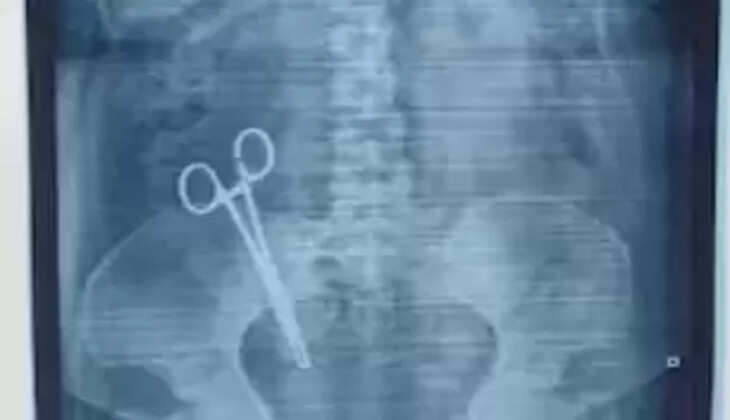

17 ஆண்டுகளாக பெண் வயிற்றுக்குள் கத்தரிக்கோல்!

உத்திரப்பிரதேச மாநிலத்தில் லக்னோவில் ஷி மெடிக்கல் கேர் என்ற மருத்துவமனை அமைந்துள்ளது. இந்த ஹாஸ்பிடலில் 2007 ல் சந்தியா என்ற பெண்ணுக்கு குழந்தை பிறந்தது. அந்த பெண் ஆப்ரேஷன் மூலமாக குழந்தையை பெற்றெடுத்த நிலையில் அது முதலே 17 வருடங்களாக தீராத வயிற்று வலியில் இருந்துள்ளார். இதற்காக அவர் பல மருத்துவர்களிடம் சிகிச்சை பெற்ற போதிலும் பலன் இல்லை. இந்நிலையில் தற்போது சந்தியா வேறொரு பிரச்சனைக்காக மருத்துவமனைக்கு சிகிச்சைக்காக சென்றிருந்தார்.

அவர் லக்னோ மருத்துவக் கல்லூரியில் தன்னுடைய வயிற்றில் எக்ஸ்ரே எடுத்து பார்த்தார்.அப்போது வயிற்றில் ஒரு கத்திரிக்கோல் இருந்தது கண்டறியப்பட்டது. மார்ச் 26 ம் தேதி சந்தியாவுக்கு ஆப்ரேஷன் செய்து கத்திரிக்கோலை மருத்துவர்கள் அகற்றியுள்ளனர். இந்நிலையில் தன்னுடைய மனைவிக்கு பிரசவம் பார்த்த டாக்டர் புஷ்பா ஜெய்ஸ்வால் மீது தற்போது அவருடைய கணவர் காவல் நிலையத்தில் புகார் கொடுத்தார்.

அந்த மருத்துவரின் அலட்சியத்தால் கிட்டத்தட்ட 17 வருடங்களாக தன் மனைவி தீராத வேதனையில் இருந்ததாக அவர் தன் புகாரில் கூறியுள்ளார். அந்த புகாரின் படி வழக்கு பதிவு செய்த காவல்துறையினர் தீவிர விசாரணை மேற்கொண்டு வருகின்றனர்.